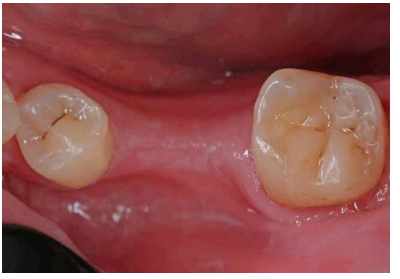

Se realizaron revisiones a 1 mes, 6 y 18 meses (Figuras 9 y 10), observando en la última radiografía de control mejoría en la lesión apical de la raíz distal. En todas las revisiones, la paciente se encontraba asintomática, la prueba de sensibilidad al frío fue fisiológica, al igual que la prueba de palpación, percusión y de mordida. El sondaje y la movilidad continuaban fisiológicos.

En el caso clínico expuesto, no se pudo realizar la revisión de los 12 meses debido a la situación de emergencia sociosanitaria causada por la COVID-19. A los 18 meses la paciente está asintomática, no presenta molestias a la palpación o percusión ni tumefacción y responde adecuadamente a la prueba de sensibilidad al frío. Radiográficamente no presenta signos de reabsorción interna ni patología periapical. Se considera que el tratamiento ha sido un éxito a nivel clínico y radiográfico2 .